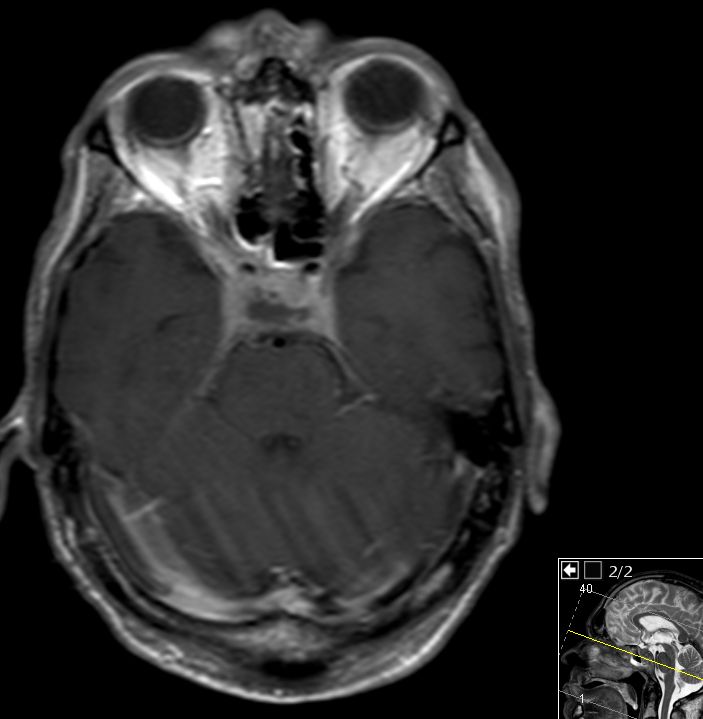

55-jähriger Mann, der vor 6 Monaten wegen eines Oropharynxkarzinoms links pT3 pN0 M0, L1, V0, Pn1 radikal operiert wurde und eine postoperative Radiochemotherapie mit Cisplatin erhielt. Jetzt Schädelbasis-Metastase im Bereich des Sinus cavernosus. Klinisch Hirnnervenausfälle links N. abducens, rechts N. opticus, - trochlearis, - trigeminus 1. Ast, unsicheres Gangbild, Störung des Schluckaktes. | ||